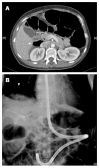

Endoscopic retrograde cholangiopancreatography (ERCP) in patients with surgically altered anatomy is challenging. Several operative interventions of both the gastrointestinal tract and the biliary and/or pancreatic system lead to altered anatomy, rendering ERCP more difficult or even impossible with a conventional side-viewing duodenoscope. Adapted endoscopes are available to reach the biliopancreatic system and to perform ERCP in patients with altered anatomy. However, both technical difficulties and complications determine the procedure's success. Different technical approaches have been described and are highly dependent on local expertise and endoscopic equipment. Standardized practical guidelines are currently unavailable. This review focuses on the challenges encountered during ERCP in patients with altered anatomy and how to deal with them. The first challenge is reaching the papilla or the bilioenteric/pancreatoenteric anastomosis in the patient with postoperative altered anatomy. The second challenge is the cannulation of the biliopancreatic system and performing all conventional ERCP interventions and the third challenge is the control of possible complications. The available literature data on this topic is reviewed and illustrated with clinical cases.